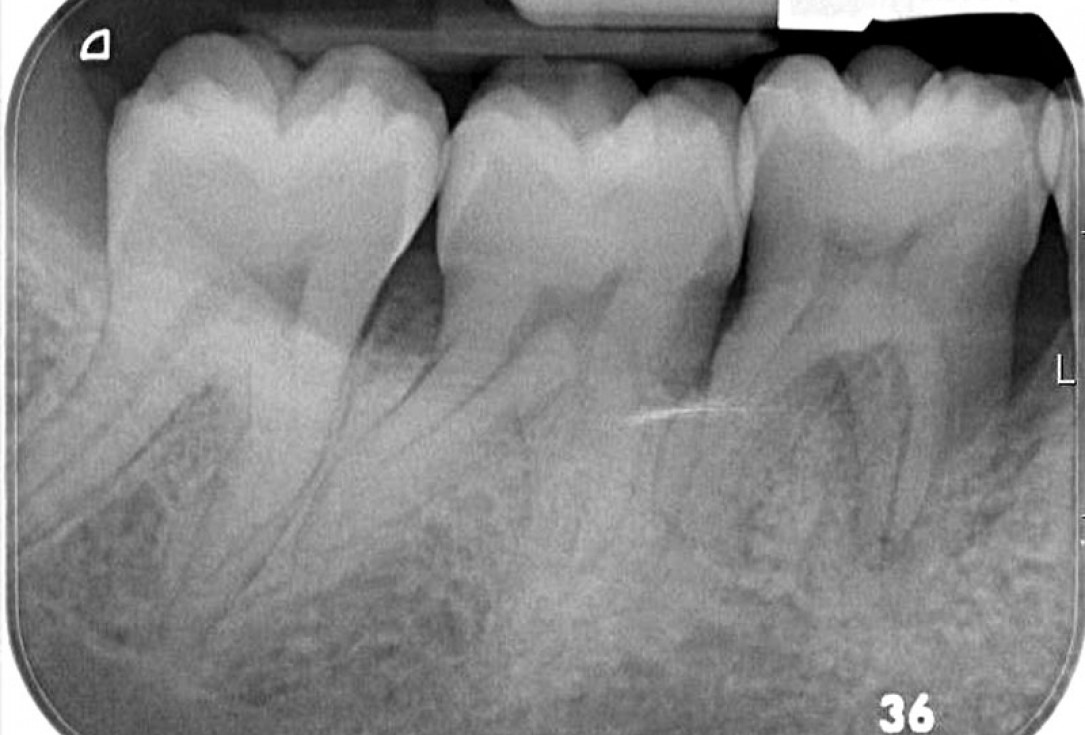

Intrabony defect treated using collprotect® membrane & cerabone® (1) - Cosgarea & Sculean

Pre-surgical probing reveals a deep intrabony defect on the distal aspect of the upper canine.